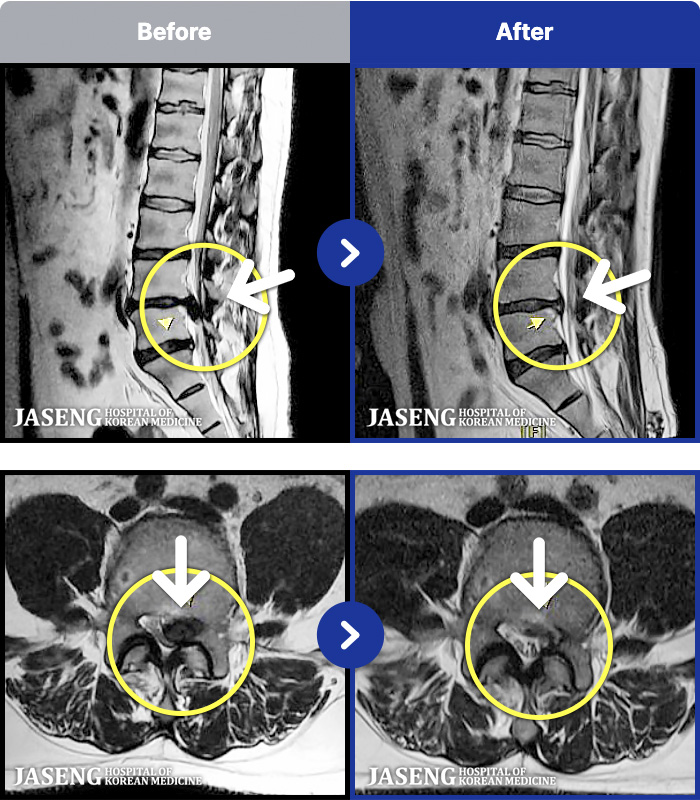

- MRI ġ

MRI ġ

96 MRI ũ ʸ Ȯϼ.